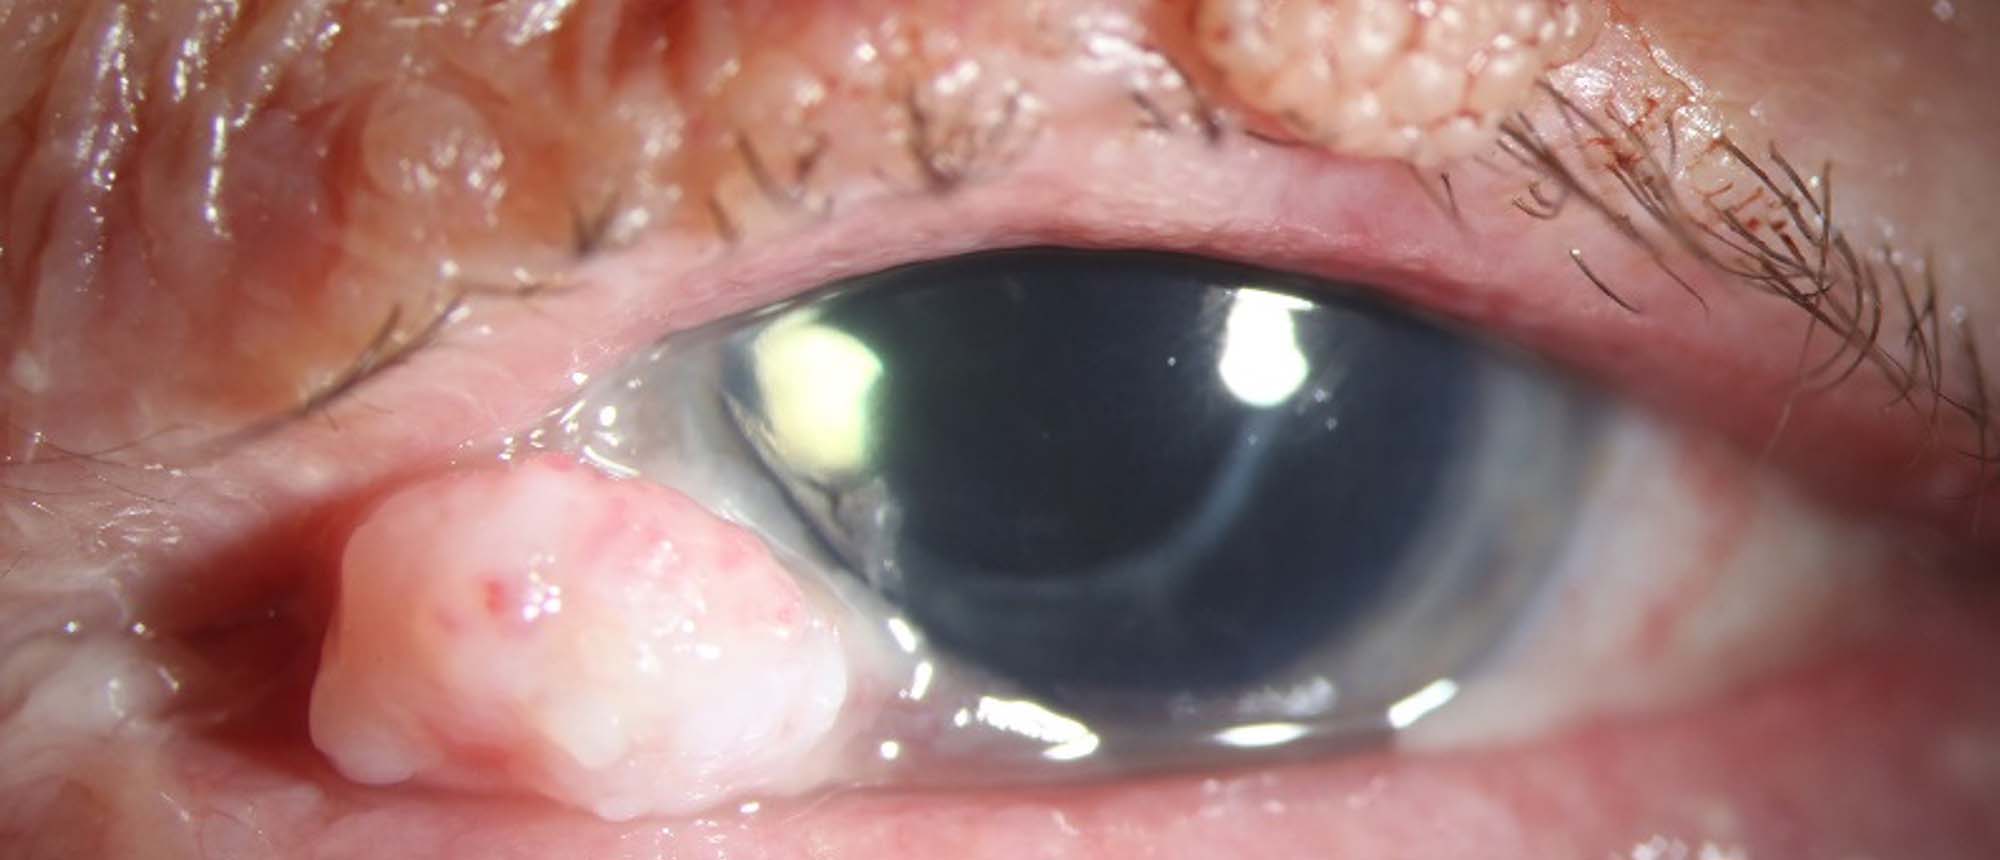

Intraosseous Hemangioma An otherwise healthy patient presented to the Emergency Room for evaluation of a left orbital rim lesion, found incidentally by an eyebrow technician. On exam, there was a firm bony mass along the superior orbital rim. Eye exam was otherwise unremarkable. CT scan of the orbi…